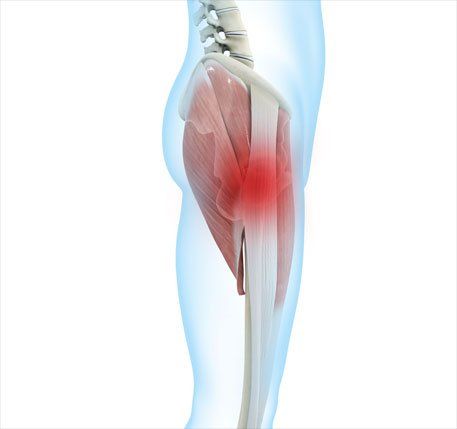

Meralgia Paraesthetica (MP) is a condition where there is irritation or pathology to the lateral cutaneous nerve of the thigh which originates from the L2 and L3 vertebrae. It courses through the pelvis to supply the sensation to the outer part of the thigh and it is at the front of the pelvis where the nerve usually becomes irritated. Symptoms can occur spontaneously or as a secondary result of surgery.

People with MP will report altered sensation such as burning, aching, coldness, shooting or pins and needles down the anterior / outer part of their hip. Symptoms can fluctuate significantly from mild symptoms to an intense ache that affects function. People typically report that symptoms can improve upon sitting, where the tension at the front of the thigh reduces.